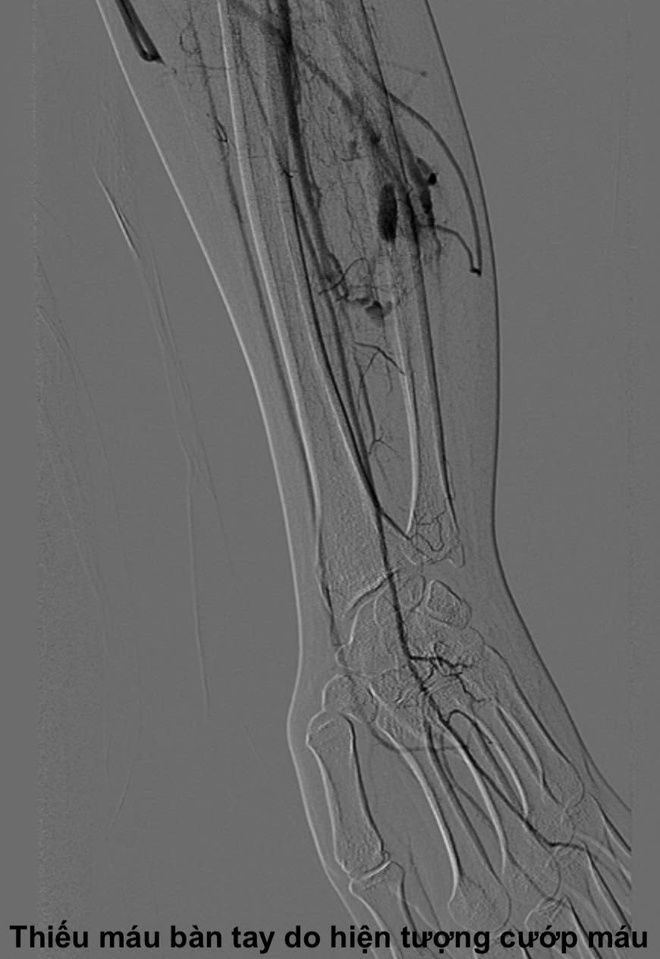

TS. Cương giải thích, dòng máu tốc độ cao đi tắt qua ổ dị dạng này sẽ không kịp cung cấp oxy và dưỡng chất cho vùng mô ở phía hạ lưu. Điều này dẫn đến hiện tượng "ăn cắp máu" (steal phenomenon), tức là ổ dị dạng hút máu từ các mạch máu bình thường lân cận, khiến các ngón tay hoặc chi bị thiếu máu nuôi mạn tính. Đây chính là nguyên nhân gây ra các triệu chứng đau, tê, sưng, nóng, hoặc thậm chí biến dạng chi của bệnh nhân Q.

Ca bệnh dị dạng động tĩnh mạch hiếm gặp.